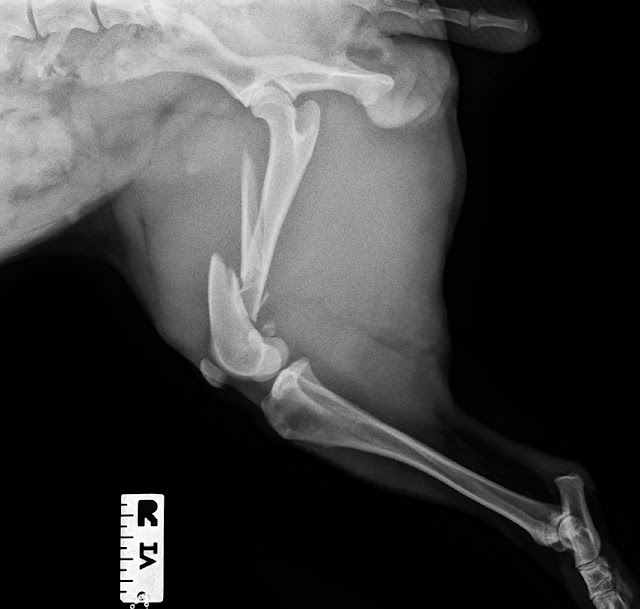

Nuestro paciente es un perro de aguas español, de 20 kg, que

saltó de una ventana y llega a la clínica con una marcada cojera de su extremidad

posterior derecha.

Comenzamos con el estudio radiográfico, y obtenemos las

siguientes imágenes:

Nuestro paciente tiene una fractura conminuta de fémur

derecho, con un gran fragmento en cuña, que intentaremos reducir y pequeños fragmentos

que no podremos recolocar, y crearán defectos de continuidad en el hueso.

Probablemente también podría sospecharse de una displasia de cadera, pero

puesto que el paciente caminaba normal antes del traumatismo, no nos vamos a

centrar en ese punto.